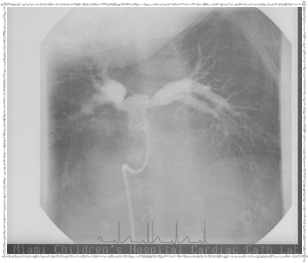

First Catheterization — Dr. Evan Zahn

In 2003, Elyse underwent a catheterization procedure at Miami Children's Hospital, performed by Dr. Evan Zahn. Below are some pictures that Dr. Zahn provided. She left the hospital the same day — remarkable!

Catheterization 2003 - Before

Before the procedure